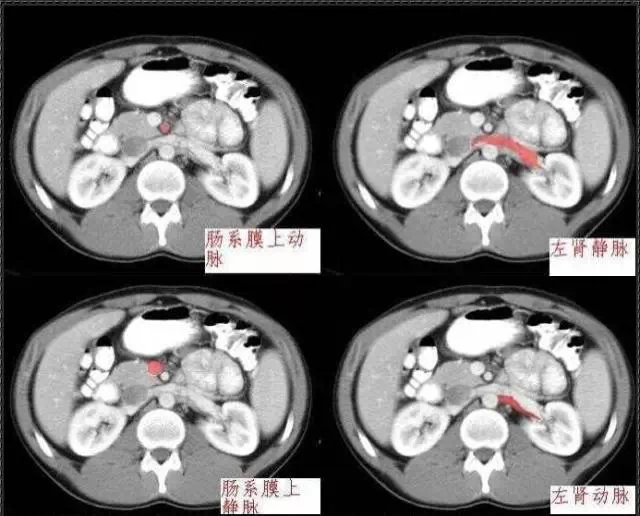

秒懂:腹部 CT 看這篇就夠